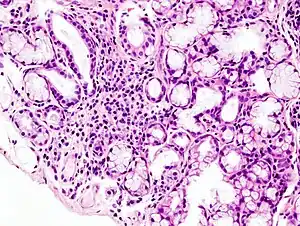

| Image with a microscope of focal lymphoid infiltration in the minor salivary gland associated with Sjögren's syndrome. | |